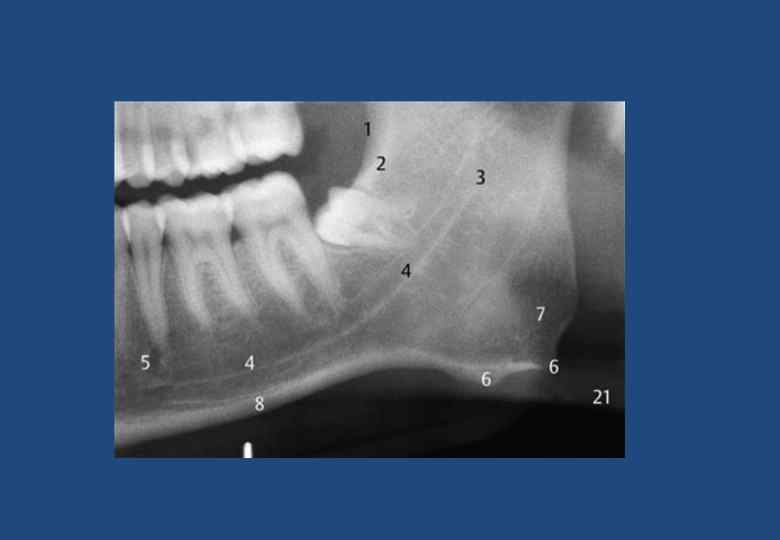

• • • • • • 1. Наружная косая линия (продолжение переднего края в каудальном и боковом направлениях) 2. Височный гребень с ретромолярным треугольником 3. Нижнечелюстное отверстие 4. Нижнечелюстной канал 5. Подбородочное отверстие 6. Угловой отросток на жевательной бугристости 7. Угол нижней челюсти 8. Компактное вещество в основании нижней челюсти 9. Подъязычная кость с ее большим рогом 10. Шейный отдел позвоночника с отчетливо видимыми замыкающими пластинами тел позвонков 11. Верхнечелюстная пазуха (границы) 12. Спинка языка 13. Медиальный полюс суставной головки 14. Латеральный полюс суставной головки 15. Венечный отросток в суперпозиции к крыловидному отростку, бугру верхней челюсти и тканям небной занавески 16. Шейка мыщелкового отростка 17. Небная занавеска 18. Тень крыши неба и тел носовых раковин 19. Верхний отдел глотки 20. Длинный оссифицированный шиловидный отросток 21. Тень компактного вещества противоположной стороны челюсти